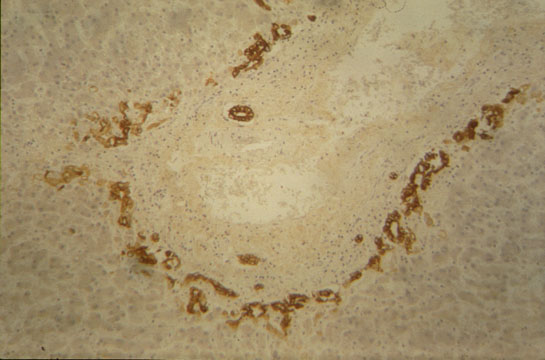

Fig 8 - BILE CANALICULI

They drain bile from the hepatocytes to the portal space. Microscopically visible only when distended by bile. Can also be demonstrated by Gomori's reaction for alkaline phosphatase and silver impregnation. Their wall is made by the plasma membrane of two adjacent hepatocytes which form intracanalicular villi. They form an intricate anastomotic network of canals.